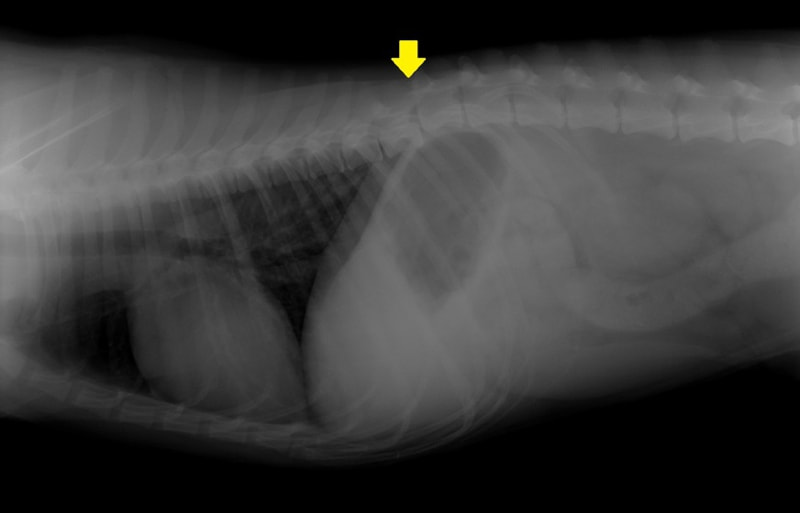

症例3:キルシュナーワイヤーのピンニングによる整復

ペルシャ猫 11ヶ月齢 雄

他院にて左大腿骨遠位の成長板骨折(salter-harrisⅠ型)が認められており、治療相談を目的として来院。当院にて、キルシュナーワイヤーを用いたピンニングにより骨折部位の整復を行いました。術後の経過は良好で、現在も経過観察中です。

術前レントゲン